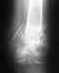

Re: Трехлодыжечный перелом левой голени

Отказ от операции по поводу перелома лодыжек из-за эндопротеза тазобедренного сустава - мягко говоря, не самое разумное решение.